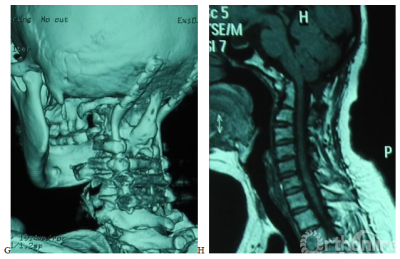

图1. 女,50岁,合并颈2/3分节不全,类风湿关节炎病史13年。A,术前X片示齿突向头侧移位,突入枕骨大孔内;B,术前CT示寰枢关节间异常骨性连接,齿突向上移位,超过McRae线7.02mm;C,术前T2加权MRI示上颈髓受压,CMA为109度; D,E术后X片及CT示齿突复位,低于McRae线9.89mm;F,G术后3年CT及三维重建示齿突复位得到维持,枕颈牢固融合;H,术后3年T1加权MRI示上颈髓受压解除,CMA改善到到155度。